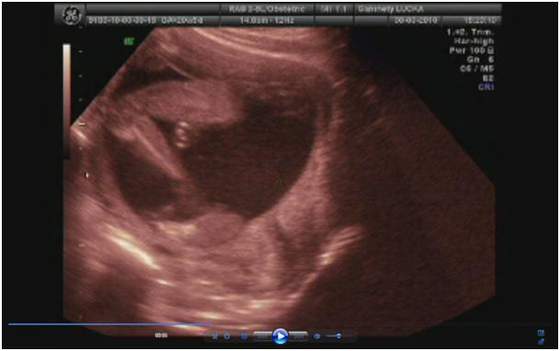

a lekarz na to "bardzo serdecznie zapraszam"

no niby 3500 ale to raczej mało możliwe (sam przyznał) skoro 2 tygodnie temu miała 2700

ale usg było jakie było i kazał się tym nie sugerować -ważne że urosła

Witam, ja też po wizycie, wszystko u nas ok, maluch ma już prawie 1 kg tzn 970g- olbrzym niesamowity!